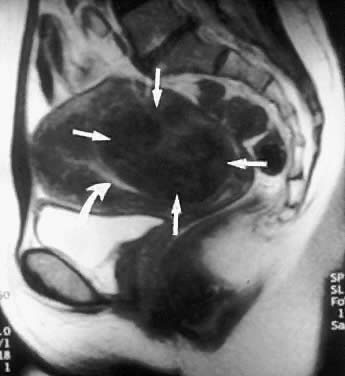

MRI is a highly accurate technique for evaluating uterine leiomyomas, adenomyosis, and uterine anomalies.13–15 T2-weighted images clearly delineate the myometrium, junctional zone, and endometrium, allowing highly accurate mapping of the size, location, and degree of myometrial involvement of uterine leiomyomas (Figs. 4 and 5). It is much more accurate in identifying and mapping adenomyosis. The major limitations of MRI imaging are cost and delays in scheduling examinations.

Fig. 5. This sagittal MRI image reveals a large intramural leiomyoma (small arrows) displacing the endometrial cavity anteriorly (curved arrow). This intramural leiomyoma involves the entire uterine wall and is categorized as T-III.